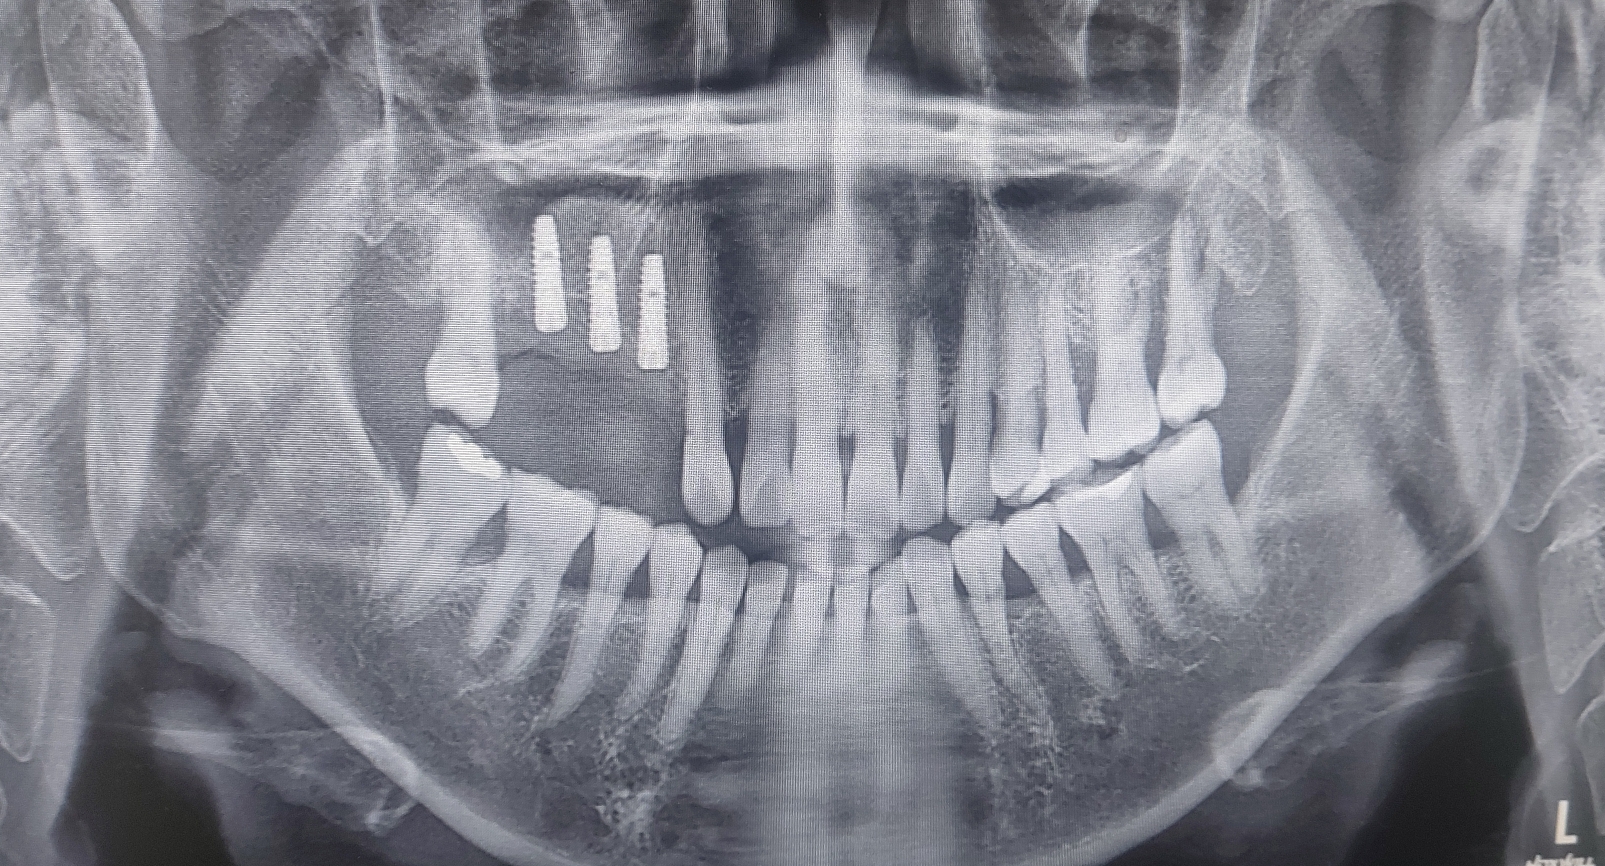

이번 증례는 기존 브릿지의 탈락으로 내원하신 환자분입니다. 오른쪽 구치부의 탈락으로 저작이 불편하신 채로 내원 하셨습니다.

환자분과 보호자분께 상세히 설명드리고 자기치아뼈이식 상악동 거상술 그리고 수면마취로 진행해드렸습니다.

각과정별로 상악동 거상술이 어떤 것인지 쉽게 알 수 있을 것입니다.

이번 포스팅에서는 사진을 보면 막연하던 상악동거상술이 어떻게 진행되었는지를 알 수 있습니다.